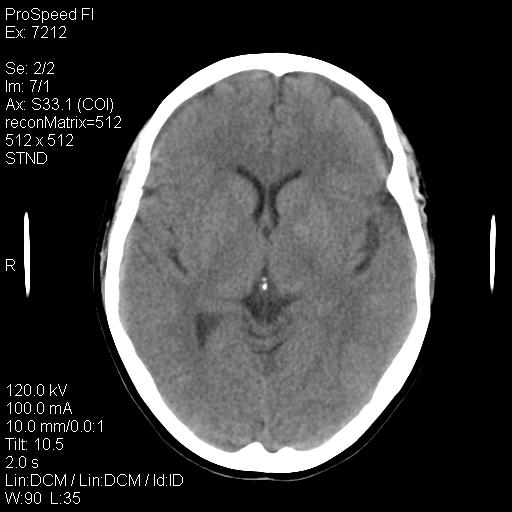

标题: CT18636:F 44Y,头痛三个月,左侧肢体麻木一周。临床诊断, [打印本页]

标题: CT18636:F 44Y,头痛三个月,左侧肢体麻木一周。临床诊断,

右额叶脑沟变浅,脑表面见新月形稍高密度影,考虑慢性硬膜下出血可能。

额顶骨多发穿凿样骨缺损区,不排除骨髓瘤等改变,进一步检查。

1)考虑左侧额部慢性硬膜下血肿(或硬膜下积液)。2)颅骨骨髓瘤不排除;建议行进一步检查。

1)考虑左侧额颞部及右侧额部慢性硬膜下血肿(或硬膜下积液)。2)颅骨骨髓瘤不排除;建议行进一步检查。

1)右侧半卵圆中心腔隙性脑梗塞。2)考虑左侧额部慢性硬膜下血肿(或硬膜下积液)。3)颅骨骨髓瘤不排除;建议行进一步检查。

腔梗